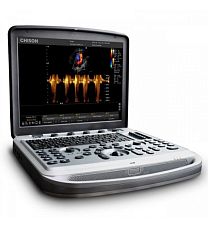

Режимы визуализации

- 2D

- М-режим (в т.ч. в режиме реального времени)

- Анатомический М-режим

- Цветной М-режим

- Энергетический допплер

- Цветной режим сравнения

- Двойной режим

- Обработка сигналов с оптимизацией 2D и потока сигналов

- Интеллектуальный допплер

- Прямое сравнение

- Пакет визуализации тканевых гармоник

- Визуализация гармоник с инверсией импульса

- Режимы SonoCT и XRES способствуют повышению качества изображений и снижению шума

Объединяя в режиме реального времени несколько изображений, полученных под разными углами, функция SonoCT создает одно высококачественное изображение. Технология SonoCT подавляет большинство артефактов, присущих обычному УЗИ, а технология XRES создает изображения, практически не содержащие шумов и отличающиеся высоким качеством и резкостью контуров.